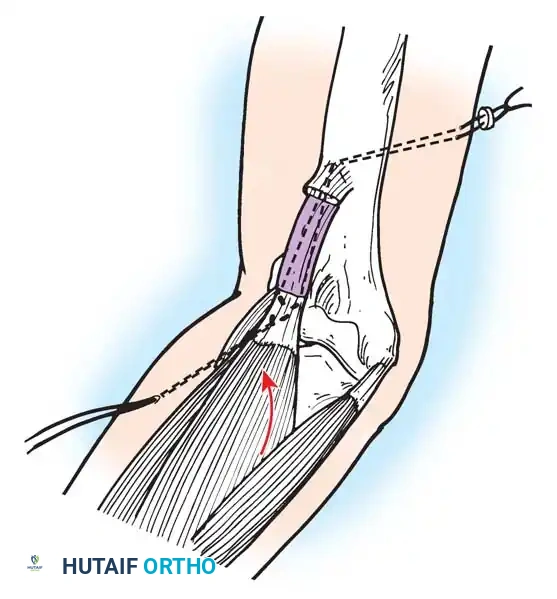

Tendon Transfers for Quadriceps Paralysis:

If the hamstrings are strong (Grade 4 or 5), the biceps femoris and semitendinosus can be transferred anteriorly to the patella or tibial tubercle.

Image

The tendons are mobilized, routed subcutaneously, and woven into the quadriceps tendon or fixed directly to the patella. Postoperatively, the knee is immobilized in extension for 6 weeks, followed by aggressive rehabilitation to achieve phasic conversion of the hamstrings from flexors to extensors.